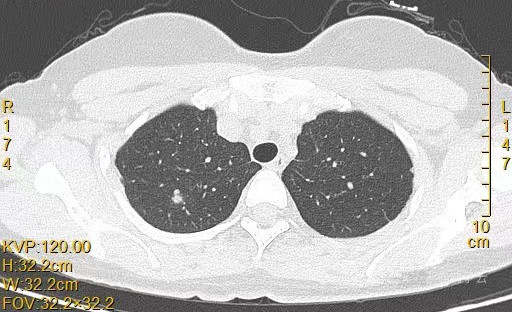

患者女,44岁,无特殊症状,做体检时发现右肺结节。查到1年前的体检CT片,右上肺当时就有一个直径约3mm的微小结节。两次检查检查图片如下:

以下三张为1年前CT片: